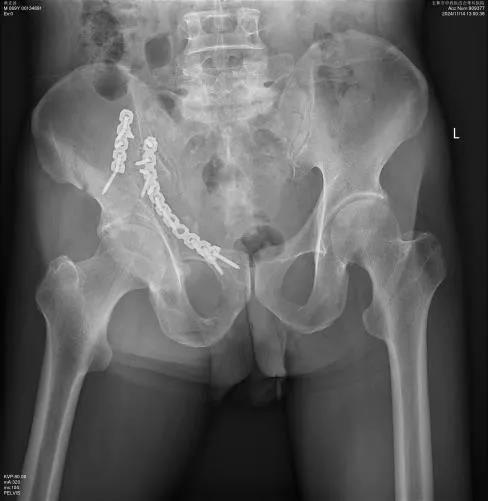

术中:患者于2024年11月1日在全身麻醉下行右髋臼骨折微创切开复位内固定治疗。术中采用腹直肌外侧入路,快速进入盆腔,根据3D打印模型预演操作对骨折进行精准复位,准确放置钢板及置钉。术中出血约600ml,术区切口仅仅6cm。

▲患者术后影像资料